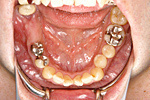

症例 11

① 左右の奥歯がありません。普通では左右つながった取り外しの入れ歯しか入りません。

② インプラントで固定式の義歯ができました。自分の歯に近い感じで食事ができます。

60才代 女性

総額:182万円(税別)

治療期間:6ヵ月

リスク副作用:メインテナンス不良ですと歯周炎、インプラント周囲炎になります。セラミックが欠けることがあります。